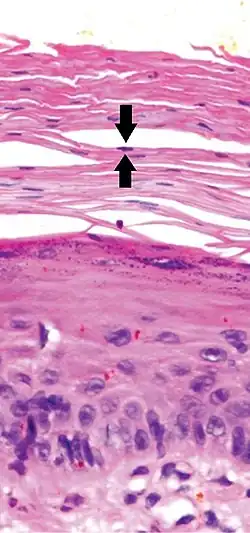

In contrast, hyperkeratosis (pictured) may also show a heterogeneous stratum corneum, but a preserved granular layer is seen.